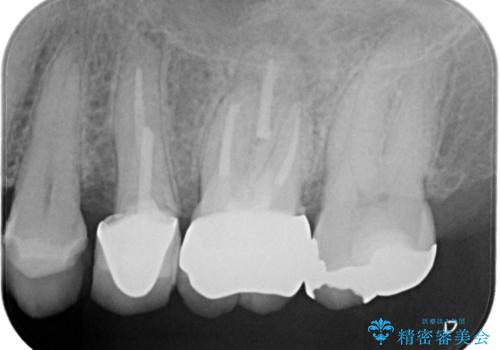

- 左上7番の銀歯の下に虫歯が発見されたケースです。患者様は機能性と審美性の両方を考慮し、オールセラミッククラウン(スタンダード)での修復を選択されました。オールセラミッククラウンは、天然歯に近い透明感を持ち、金属を使用しないため金属アレルギーのリスクも軽減されます。治療後は、違和感なく快適に噛めるようになり、自然な仕上がりに患者様も大変満足されました。

虫歯を取り除くと、歯の構造が弱くなり、破折のリスクが高まるため、修復には強度と耐久性のあるオールセラミッククラウン(スタンダード)を選択しました。